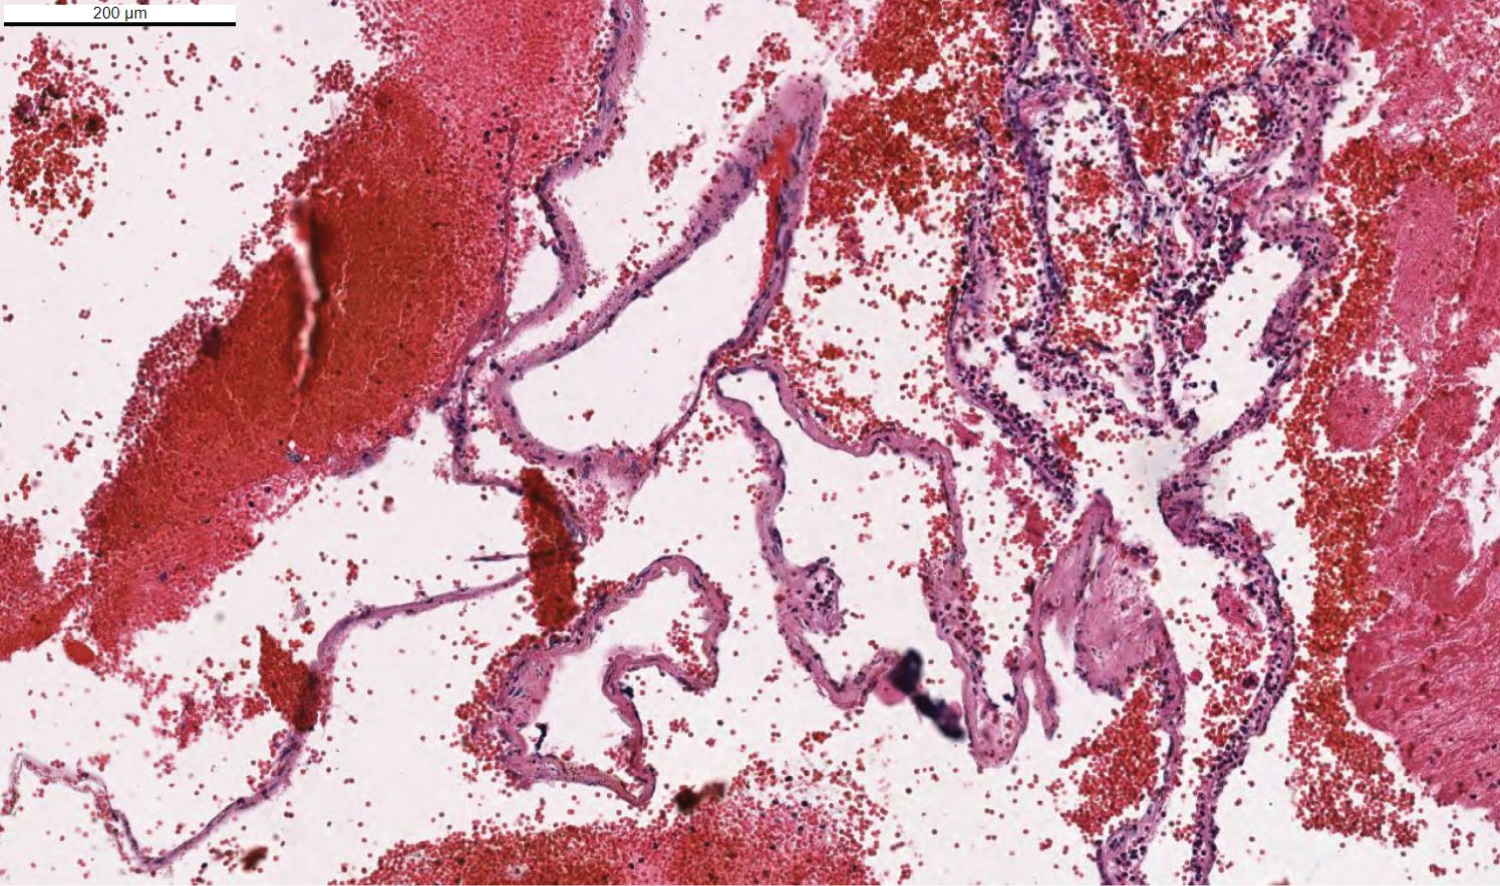

One percent of infantile hemangiomas involve the central nervous system, and approximately half of these are intracranial [8]. Most intracranial infantile hemangiomas classically involve the extra-axial basal cisterns, subarachnoid and ventricular spaces, and cavernous sinus [9]. Our case was demonstrating classically findings of infantile hemangiomas (Figure 5), but confirmation of hemangioma was made by immunohistochemical staining. Pathologic specimen was positive staining with GLUT1 and SMA which are reliable markers for infantile hemangioma. GLUT1 (Figure 6 and Figure 7), a glucose transporter present in normal capillary endothelial cells constituting the blood-brain barrier, is a particularly useful marker of infantile hemangiomas because it differentiates those from other vascular tumors and malformations that have been shown to lack GLUT1 [10]. Several other associated abnormalities have been observed in infants with infantile hemangioma, including arterial anomalies, ipsilateral cerebellar hypoplasia, Dandy-Walker malformation, Moya Moya-like proliferation of the internal carotid artery terminus [11] (Figure 6 and Figure 7).

Figure 5: Pathology prepared slides showed congested vascular lesions which has thin walls with hematoxylin eosin dye. View Figure 5

Figure 6: Hematoxylin Eosin dying of the pontine mass. Specimen showed a vascular lesion within slight walls. View Figure 6